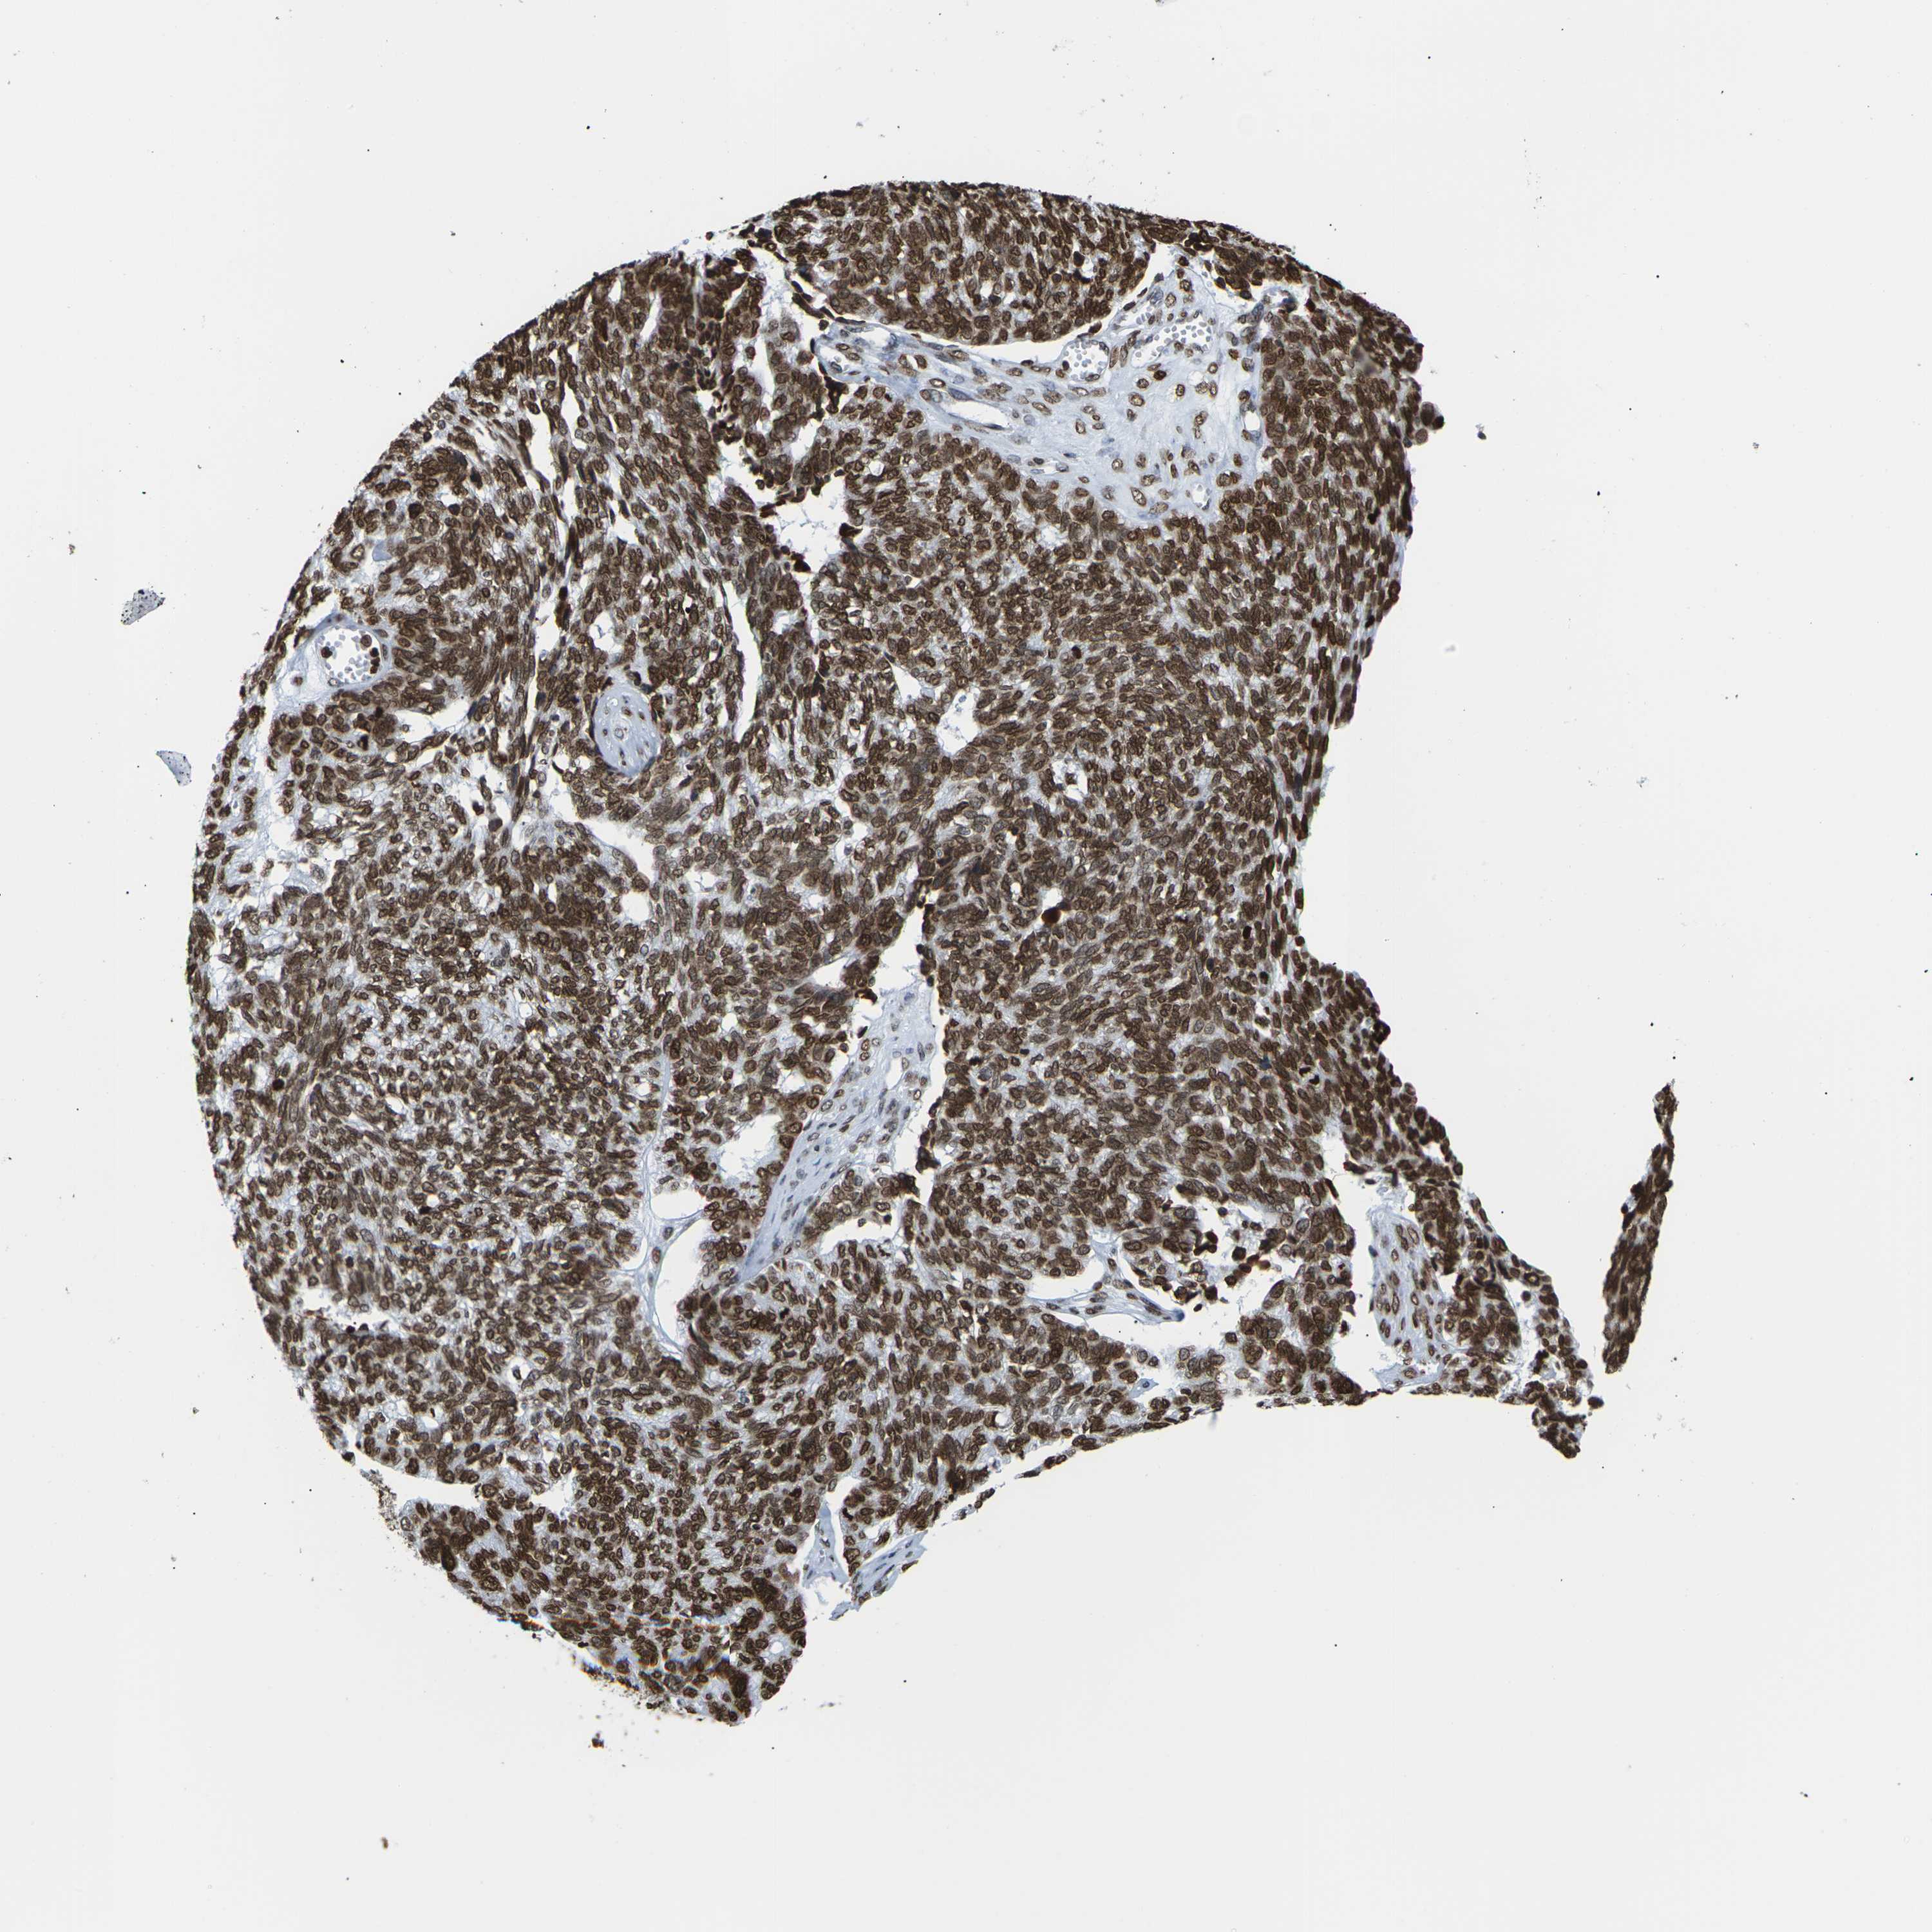

OVARIAN CANCER - Protein expressioni

A mouse-over function shows sample information and annotation data. Click on an image to view it in a full screen mode. Samples can be filtered based on level of antibody staining by selecting one or several of the following categories: high, medium, low and not detected. The assay and annotation is described here.

Note that samples used for immunohistochemistry by the Human Protein Atlas do not correspond to samples in the TCGA dataset.

Antibody stainingi

Antibody staining in the annotated cell types in the current human tissue is reported as not detected, low, medium, or high, based on conventional immunohistochemistry profiling in selected tissues. This score is based on the combination of the staining intensity and fraction of stained cells.

Each image is clickable and will lead to virtual microscopy that enables deeper exploration of all samples and also displays staining intensity scores, fraction scores and subcellular localization as well as patient and tissue information for each sample.

Antibody HPA041189

Antibody CAB011483

Staining

High

Medium

Low

Not detected

Intensity

Strong

Moderate

Weak

Negative

Quantity

>75%

75%-25%

<25%

None

Location

Nuclear

Cytoplasmic/membranous

Cytoplasmic/membranous,nuclear

Cystadenocarcinoma, serous, NOS

Carcinoma, endometroid

Cystadenocarcinoma, mucinous, NOS

Carcinoma, NOS